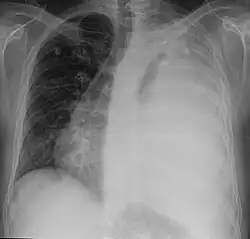

Ein Mediastinalshift oder eine Mediastinalverlagerung bezeichnet die Verschiebung des Mediastinums aus der Mittellinie des Thorax nach links oder rechts. Der Begriff wird in der Röntgendiagnostik verwendet.

Ursächlich ist entweder eine Verminderung des Volumens der Thoraxhälfte auf der Seite, zu der das Mediastinum verlagert ist, oder eine Vermehrung des Volumens auf der anderen Seite.

Ursachen für eine Vermehrung des Volumens in einer Thoraxhälfte sind zum Beispiel